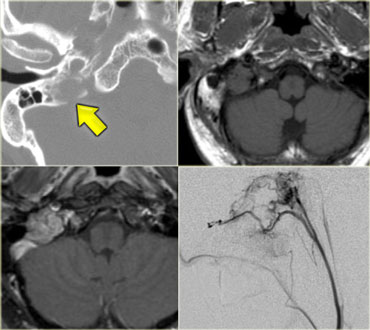

On the left an example of a Skull Base Paraganglioma.

On the left CT images of a 58-year-old male with a gradual onset of right facial pain and numbness and a recent onset of double vision.

First study the images, than continue.

There is an enhancing mass anterior to the skull base and also in the region of the right cavernous sinus.

In the bone window setting there is sclerosis of the skull base, particularly in the region of the clivus.

Continue with the MR images.

On the left enhanced sagittal and coronal T1WI.

The most striking finding is the black clivus due to the sclerosis.

A normal clivus is bright on T1WI as a result of the fatty bone marrow.

There is an enhancing mass anterior to the clivus.

On the coronal images we see the enhancement extending through the foramen ovale to the right of the cavernous sinus.

The diagnosis is a nasopharyngeal squamous cell carcinoma with intracranial extension.

The differential diagnosis would include: skull base metastasis, lymphoma, chronic infection and even a meningioma - although this would be an unusual way for a meningioma to spread.